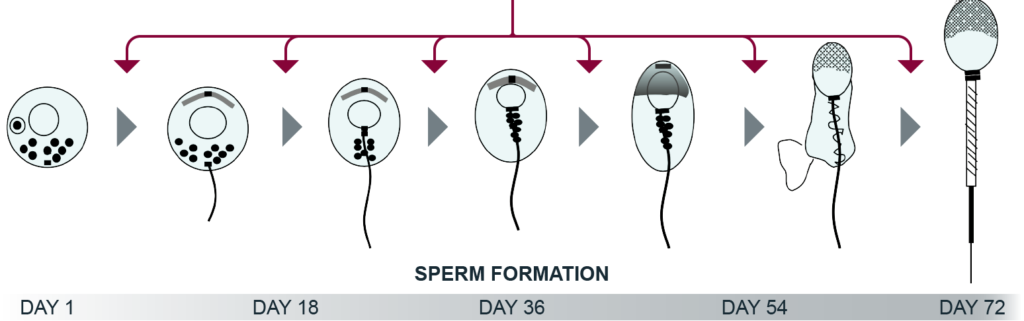

HOW SPERM PRODUCTION WORKS

Hormones play a decisive role in sperm production (=spermatogenesis). The pituitary gland generates a hormone known as follicle stimulating hormone (FSH). The luteinizing hormone (LH) is generated at the same time. While both hormones lead to the maturation of egg cells in women, in men they are responsible for the formation of sperm cells.

Therefore, sperm count can vary person-to-person. The average, sexually mature man has about two to 3 billion sperm available at any given time. But because sperm cells in the seminiferous tubules are constantly being regenerated, these reserves are always a mixed bag of sperm cells at different stages of maturity.